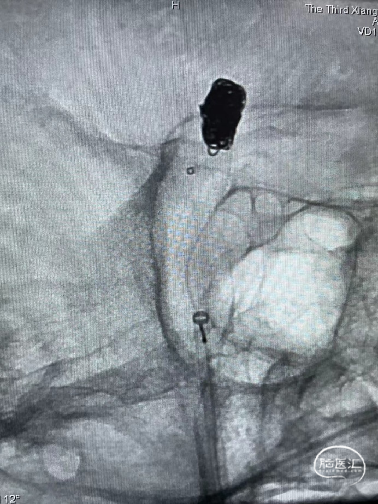

术中操作-预置支架导管+填圈:

预置支架导管

置入弹簧圈微导管

置入弹簧圈

填圈后通过微导管并释放支架

导丝通过&支架导管到位

释放支架:

支架到位

头端打开

中间打开

近端打开,后予以支架导管通过支架将其充分打开。

术后即刻复查:远端血管通畅、支架打开良好。

术后正位复查